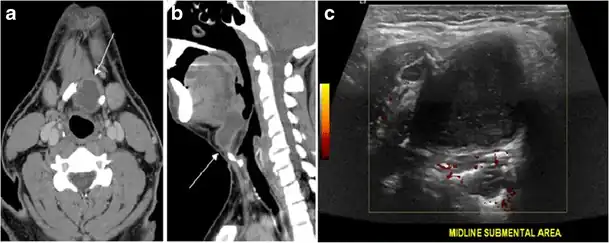

Fig. 20. Recurrent/residual thyroglossal duct cyst in a 39-year-old male patient. The first resection of thyroglossal duct cyst showed histopathology evidence of Hurthle cell type thyroid cancer. However, the second resection showed signs of chronic inflammation, with no malignant cells. a, b Enhanced axial and sagittal neck CT scans demonstrate a unilocular cystic lesion arising from the tongue base and extending through the partially resected hyoid bone. This cystic lesion has a peripheral enhancing wall, which becomes more thick over its inferior aspect associated with surrounding fat stranding at the surgical site (white arrow). There are no internal septations, nodules or masses, or calcifications. c Transverse view of power Doppler ultrasound at the submental area demonstrates cystic lesion and internal debris with no detected internal vascularity.[1]